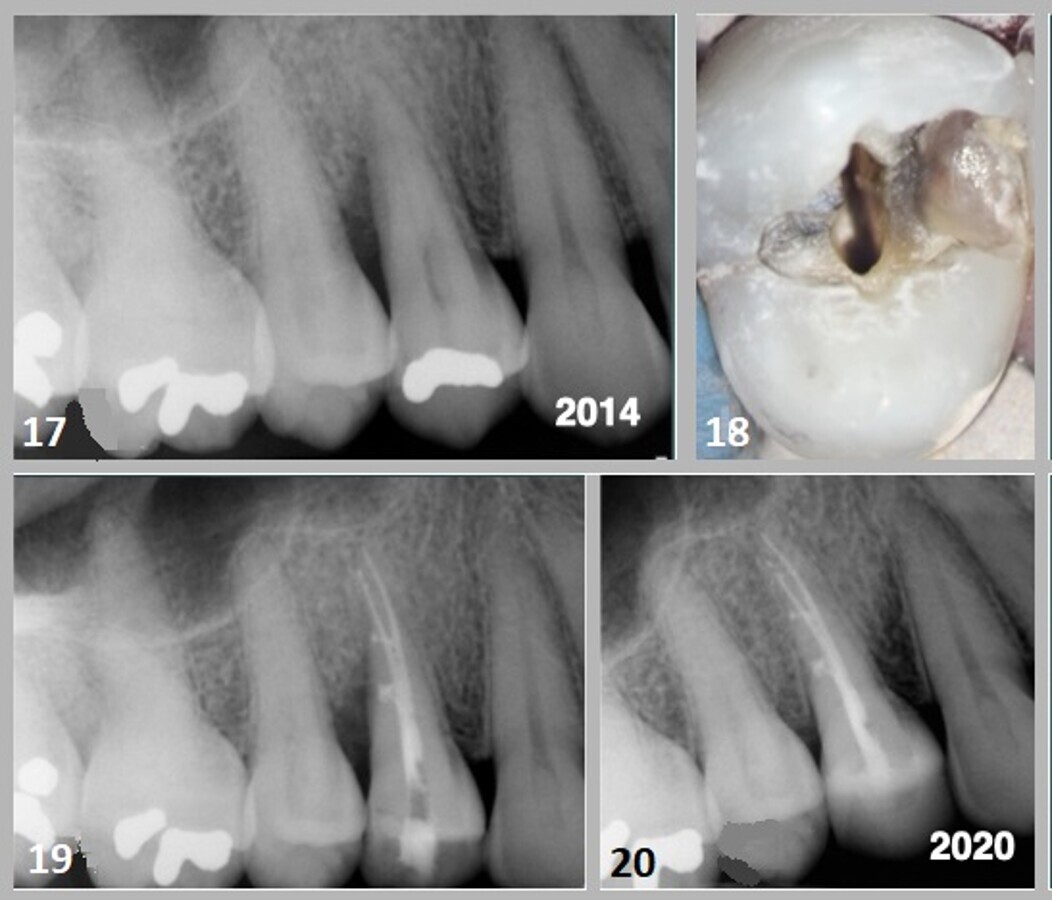

En juillet 2014, une patiente de 45 ans s'est présentée au cabinet avec comme principale plainte un gonflement de la papille distale de la dent n° 14 pendant une période de dix jours. L'examen clinique a révélé une restauration d'amalgame occlusal avec une couture palpable dans la crête marginale distale. Les profondeurs de sondage le long des angles des lignes distobuccale et linguale de la dent ont démontré une poche infra-osseuse de 8 mm. La radiographie périapicale a montré une petite restauration d'amalgame avec une radioclarté verticalement angulée interproximale entre la dent #14 et la dent #15. Une ligne de fracture s'étendant dans la crête marginale mésiale a été identifiée (Figs. 17 & 18). La vitalité de la dent a été évaluée avec des tests de pulpe thermiques et électriques, qui n'ont suscité aucune réponse.

Le traitement endodontique a été réalisé en utilisant une technique de condensation verticale chaude (Fig. 19). La préparation d'accès a été scellée avec une restauration en composite fluide et hybride à l'aide du système Bioclear Matrix développé par le Dr David Clark. La radiographie prise au recul de six ans (2020) montrait une régénération osseuse dans la zone interproximale, qui avait éliminé le défaut parodontal (Fig. 20).

Cas 4—Fig. 17 : Un défaut infraosseux de 8 mm était évident le long de la face proximale distale de la racine de la dent #15. Fig. 18 : Des débris présents dans la crête marginale distale de la dent n° 14 ont montré une ligne de fracture ; cependant, il n'y avait aucune indication de séparation cuspidienne. Le retrait de l'amalgame a révélé l'extension de la fracture dans le plan de contrainte cuspidienne de l'angle vestibulaire et axial. Fig. 19 : L'espace canalaire a été obturé à l'aide d'une technique de condensation verticale chaude. Des branches latérales du système canalaire ont été notées. Fig. 20 : Une radiographie périapicale post-opératoire prise en 2020 a montré une régénération osseuse et une reformation du ligament parodontal dans le défaut sous-osseux le long de la face distale de la racine